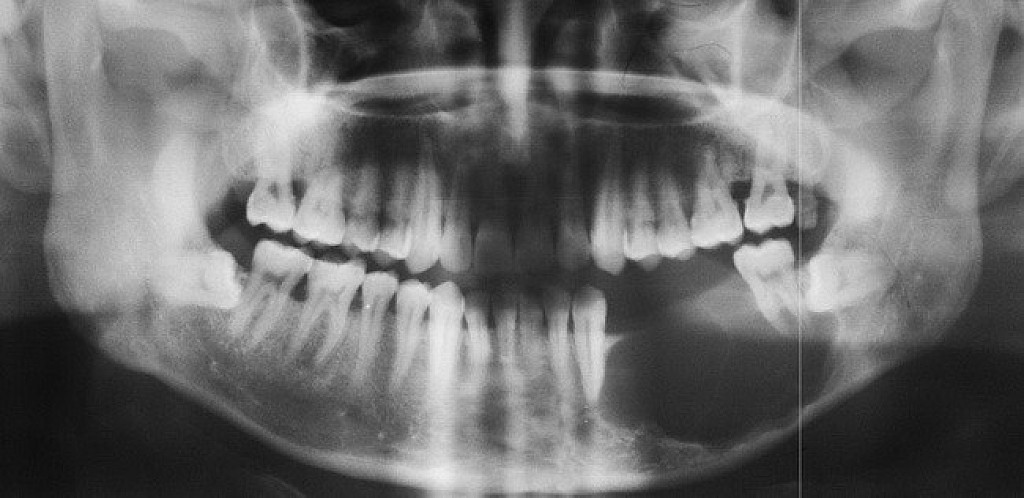

Ameloblastoma Symptoms and Diagnosis

Ameloblastoma is usually painless, with the only symptom being swelling in the area. It is usually only identified on radiographic examination in a dental office. Early developing lesions do not displace teeth or cause numbness, so the patient may not know a tumor is growing in one of their jawbones. If a potential lesion is identified on a dental radiograph, more elaborate imaging is required. This will include a CAT scan and possibly an MRI. However, the diagnosis cannot be solely determined by imaging. It requires a biopsy to make the final diagnosis. Cysts will sometimes appear similar to the ameloblastoma on the imaging.